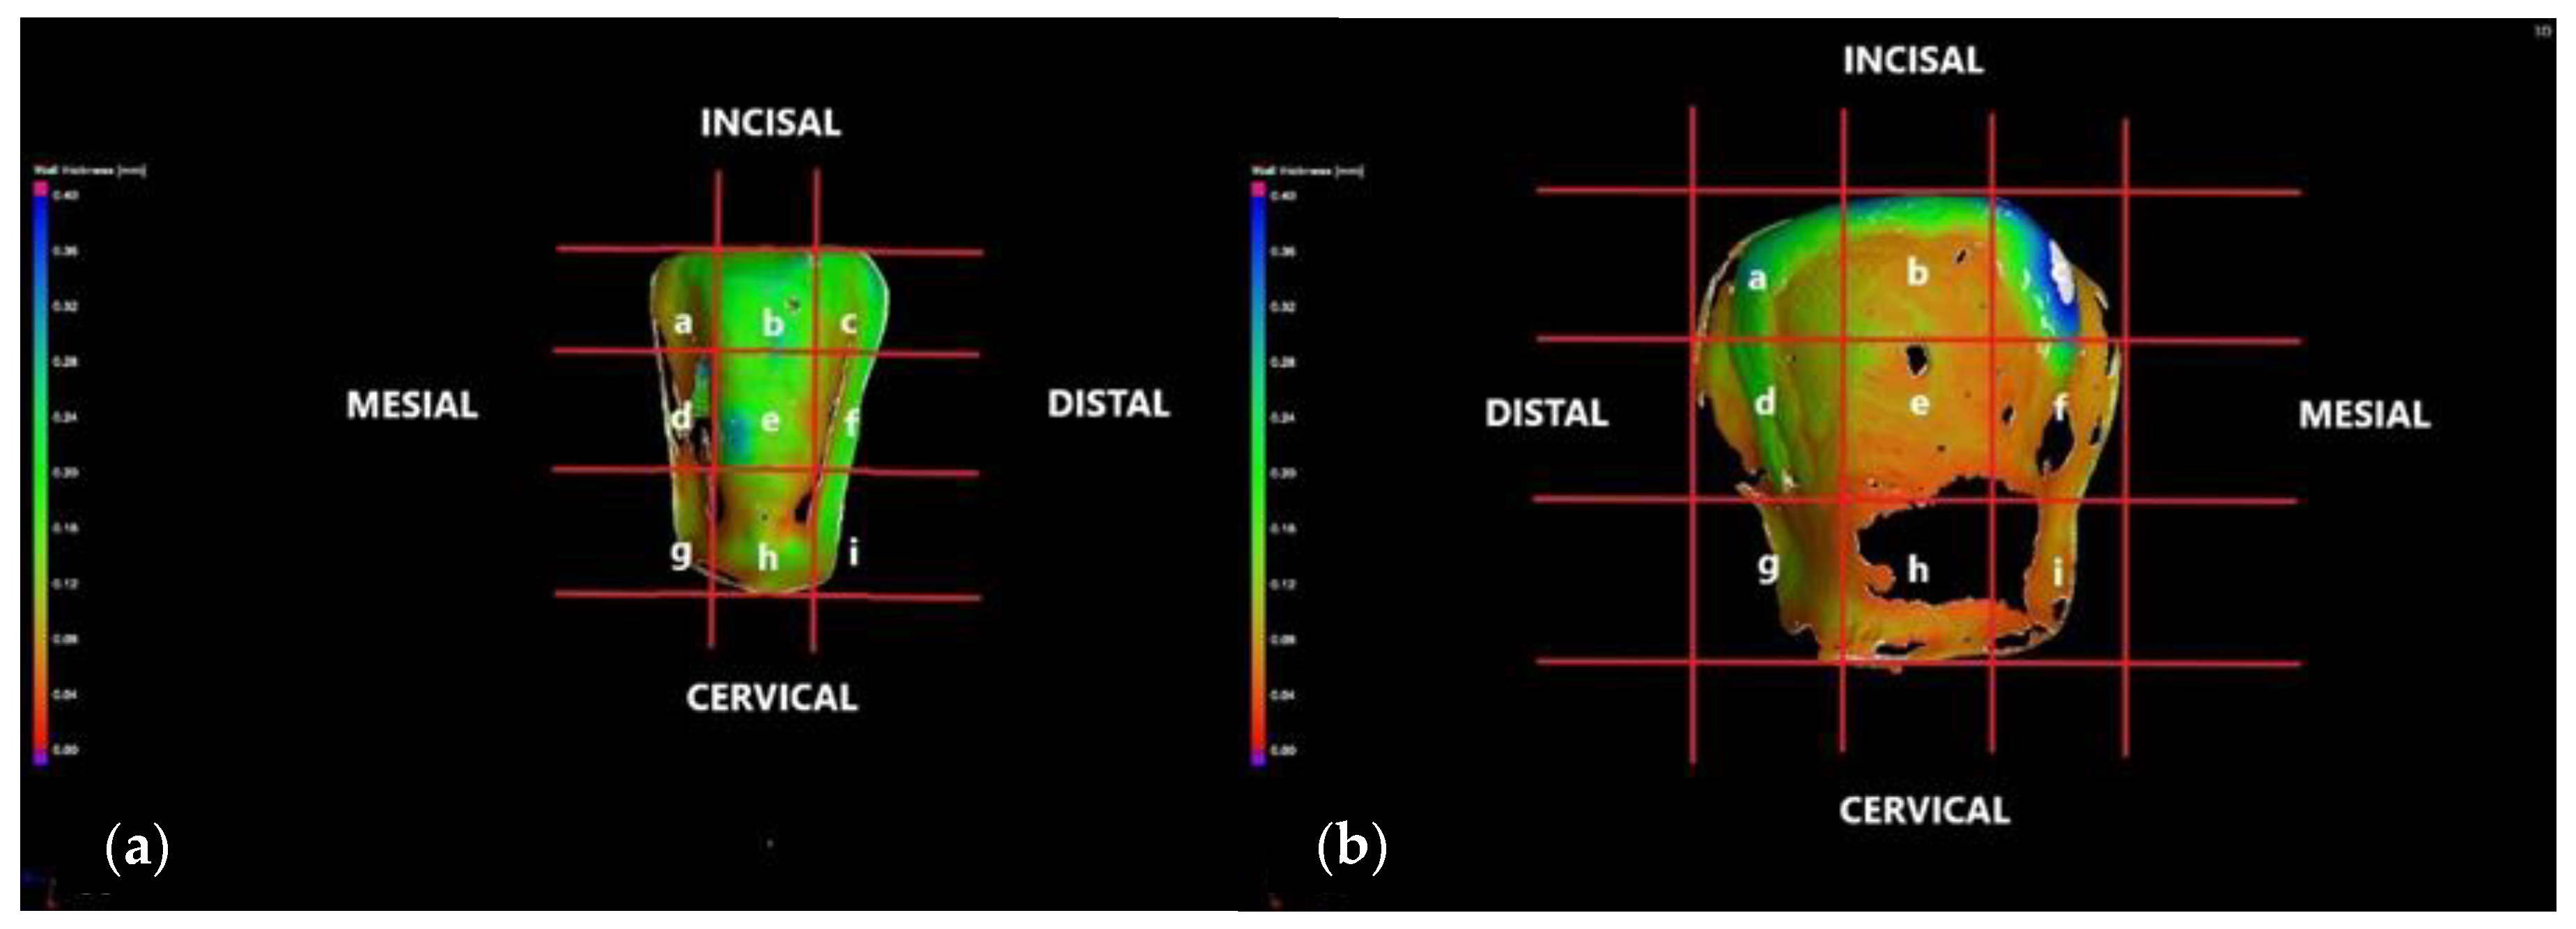

3.1. Optical Microscopy

3.2. Micro-CT